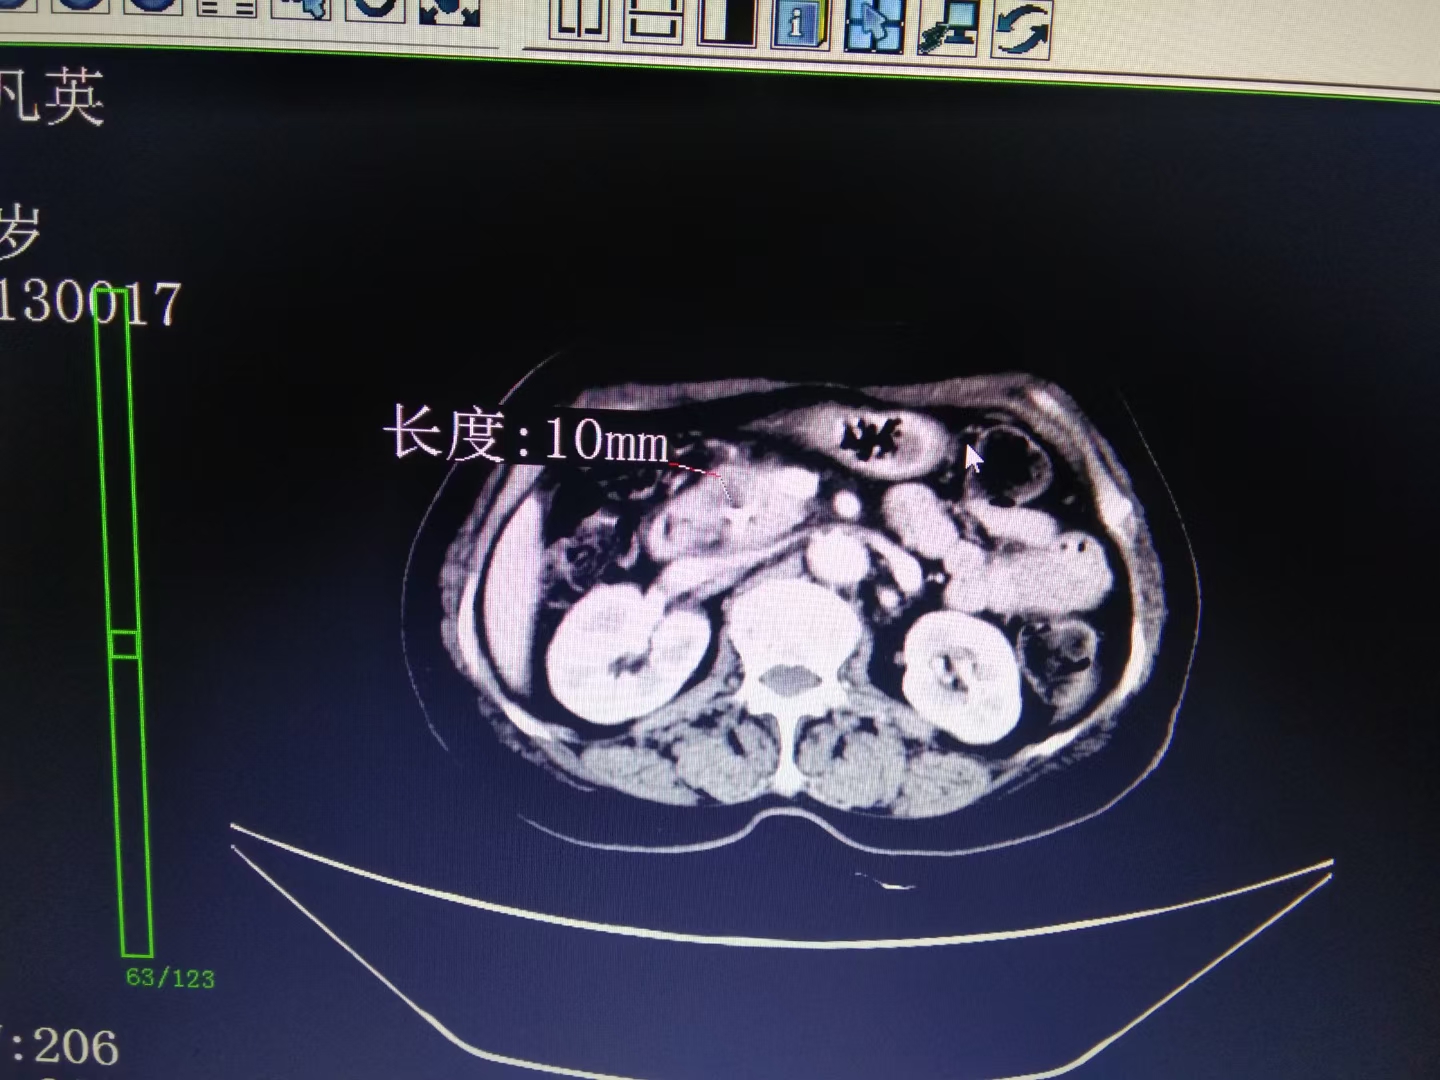

70岁曾娭毑发现1cm左右胰头部恶性结节,致胆道梗阻,在外院放了胆道支架,一直未取得病理。

我科经皮穿剌活检病理回报:胰腺癌。